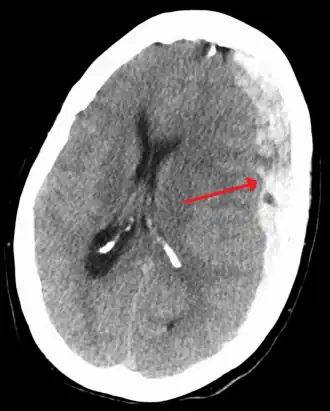

| Субдуральная гематома (обозначена стрелкой) со значительным смещением срединных структур. | |

При компьютерной томографии субдуральные гематомы имеют классическую серповидную форму, однако, могут выглядеть и линзовидно, особенно в начале кровотечения; это может вызвать затруднения в дифференциальной диагностике субдуральной и эпидуральной гематом. Более достоверным признаком субдуральной гематомы является её относительно большая распространённость по ходу полушария головного мозга с преодолением швов черепа, в отличие от эпидуральной гематомы. Субдуральная гематома также может выглядеть как «наслоение» повышенной плотности по ходу намёта мозжечка; такая гематома может быть хронической и стабильной, и косвенными минимальными признаками кровоизлияния могут служить сглаженность прилегающих борозд и медиальное смещение границы между серым и белым веществом.

Хронические гематомы при компьютерной томографии могут не дифференцироваться из-за своей изоденсивности мозговому веществу (иметь плотность вещества мозга), что затрудняет их выявление.